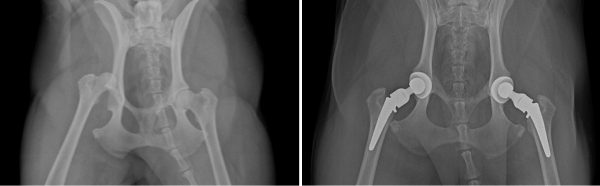

髋关节置换:近日,我院骨科专家芮医生为一只 4 岁边牧成功实施左后腿髋关节置换术。这只边牧去年曾因右后腿髋关节发育不良,在我院接受置换手术且恢复理想。今年左后腿跛行,经DR检查确诊同因髋关节发育不良,主人基于对芮光泽医生的充分信任,再次选择瑞鹏黄兴为狗狗诊疗。

芮医生团队采用威马系统为患犬进行全髋置换,成功解决患犬不能站立问题。术后第一天,狗狗便能负重行走,住院十天后顺利出院,芮医生的精湛技术不仅收获了主人的高度认可,更进一步加深了这份跨越两次诊疗的信赖。